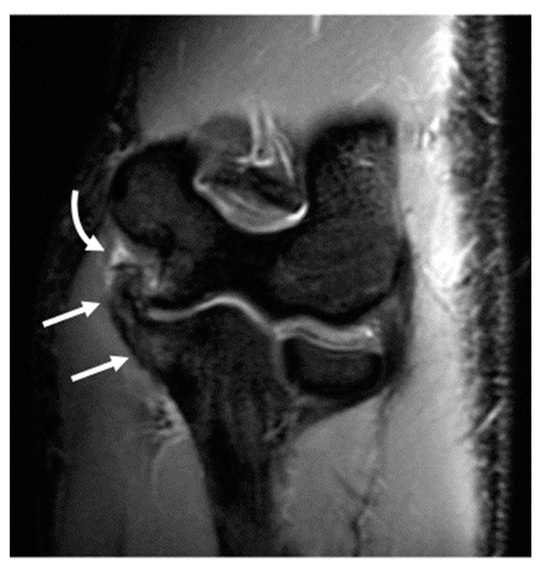

Other findings expected to occur with repetitive stresses over time, specifically ulnar neuropathy and development of an ulnar traction spur at the UCL insertion into the sublime tubercle, demonstrated an expected trend of increasing frequency with age. Ulnar traction spurs were pronounced in several athletes in subgroup 3 with professional experience (Figure 7).

Figure 7.

A 20-year-old male left-hand-dominant Major League Baseball pitcher. Coronal STIR image of the left elbow demonstrates a large ulnar traction spur with associated bone marrow edema (arrow). There is full thickness tear of the posterior band of the ulnar collateral ligament (curved arrow).